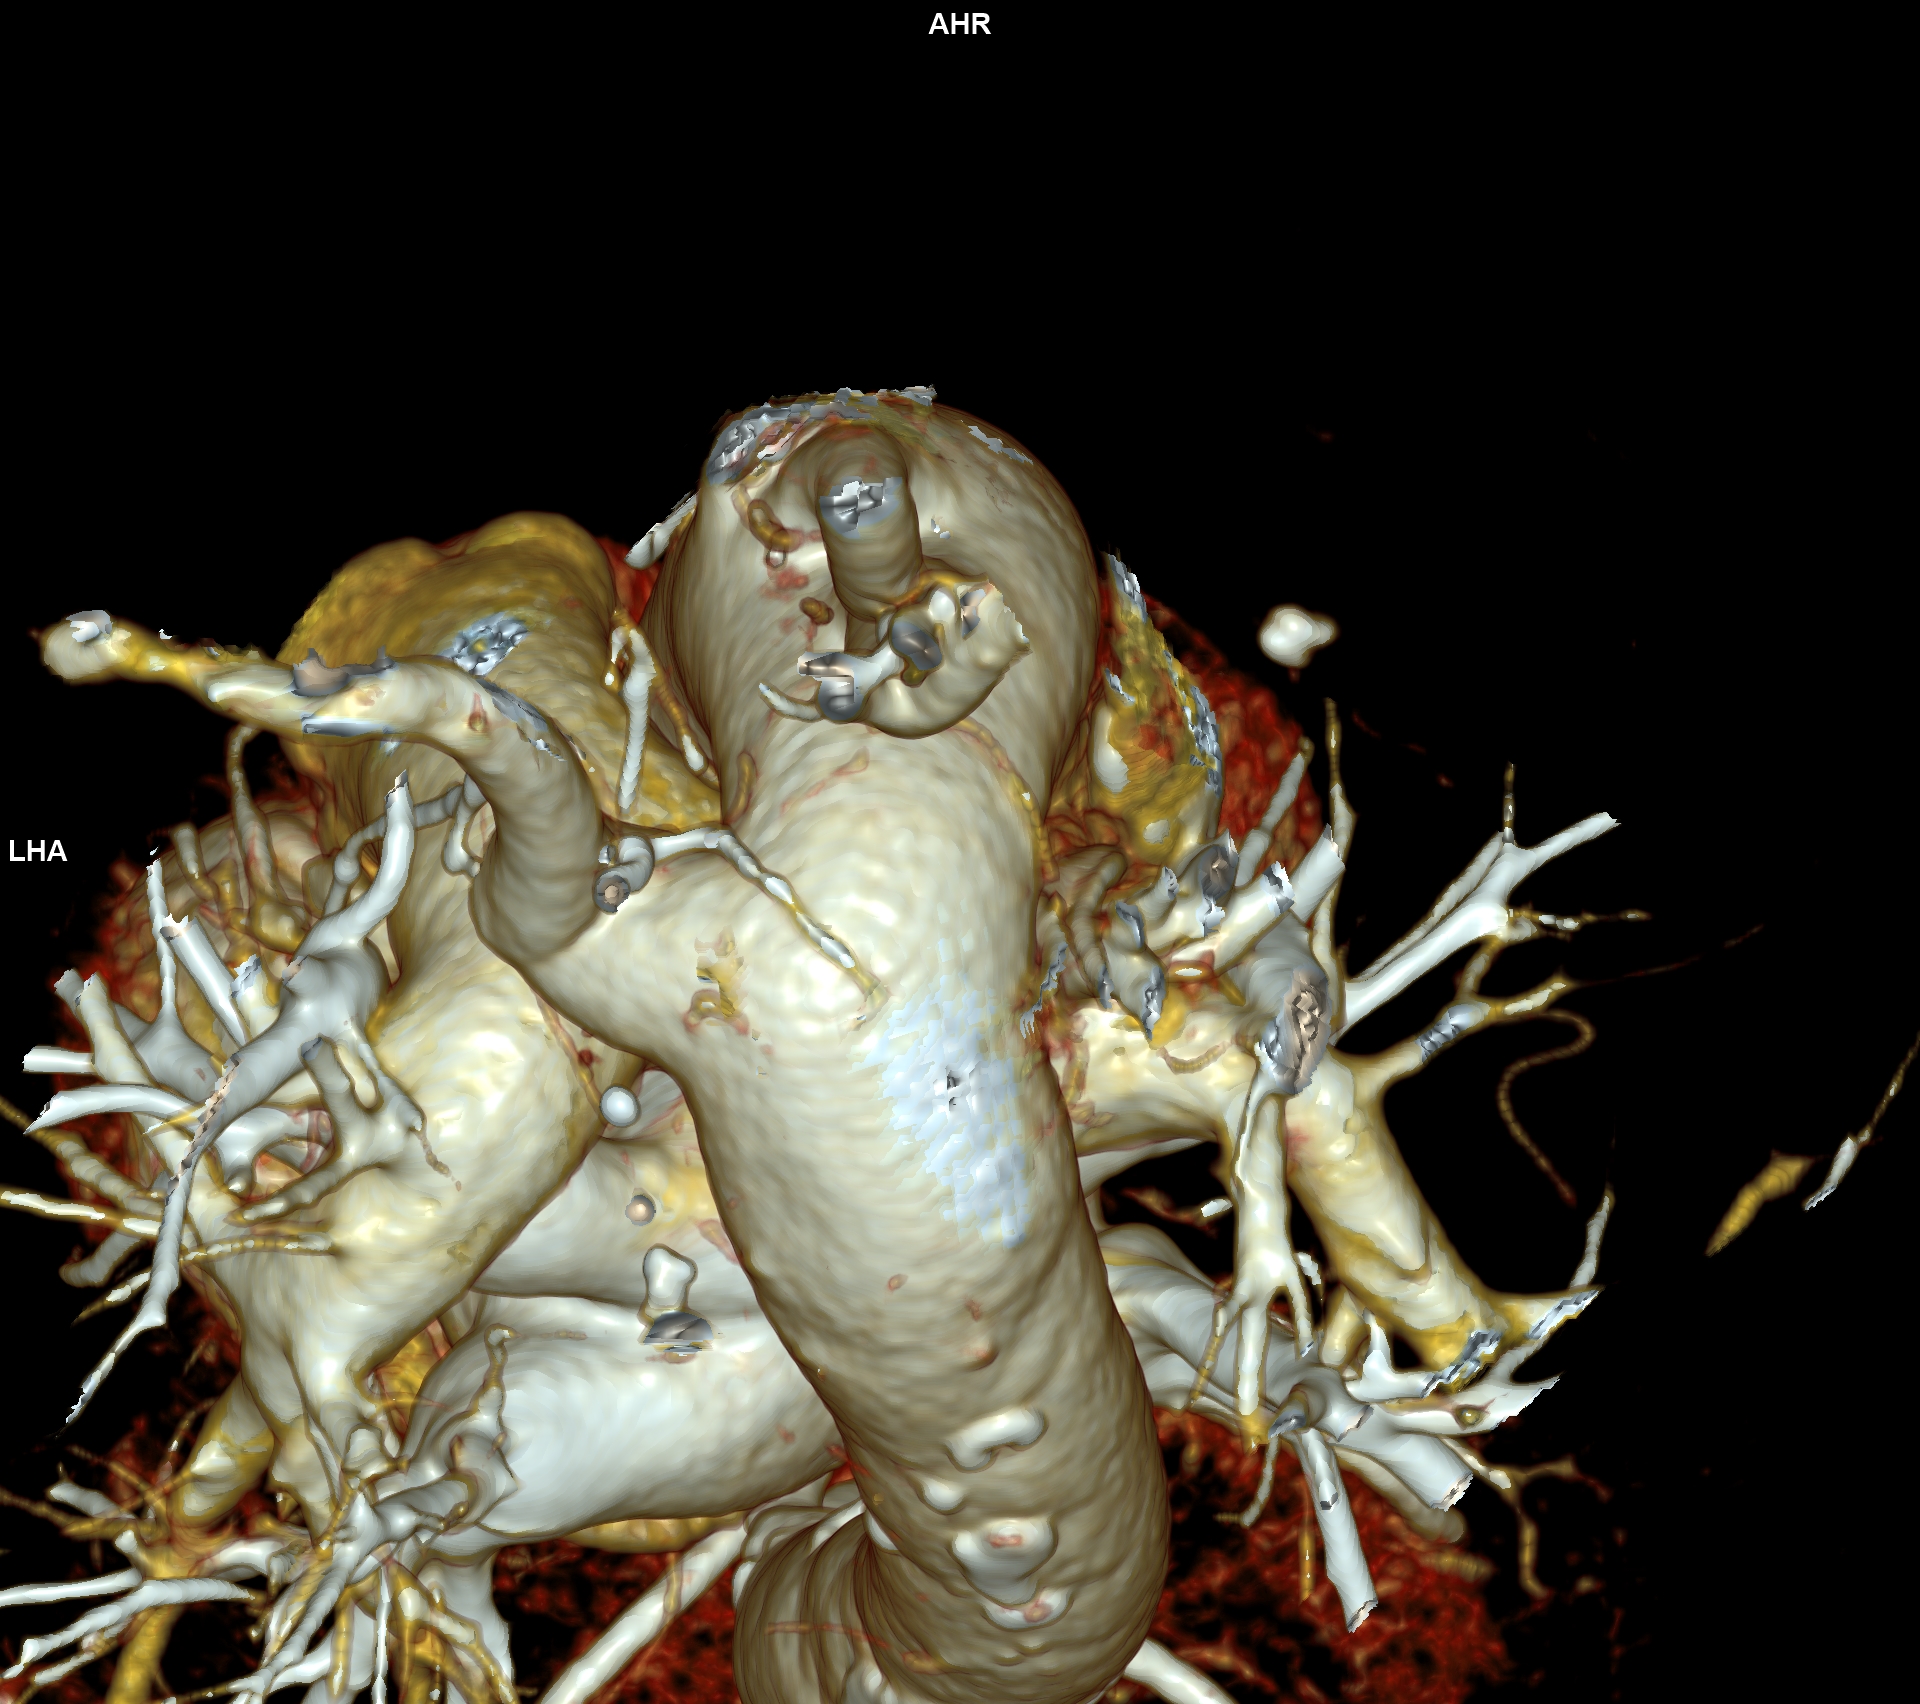

CAZ nr 57: Arc aortic de partea dreaptă si diverticul Kommerell

Figura 3, 4, 5: reconstrucție de volum 3D din achiziție angioCT toracică

Discuţie caz nr 57:  pacient asimptomatic care a efectuat angioCT de aorta toracică pentru evaluarea unei creșteri de calibru a aortei la examinarea ecocardiografica. Este o anomalie de dezvoltare a arcului aortic, ce este situat la dreapta, cu originea arterei subclavii stângi dintr-o structura diverticulară.

DE LUAT ACASĂ!!! Diverticulul Kommerell este considerat a fi o eroare de dezvoltare a celui de-al patrulea arc aortic dorsal; a fost original descris la pacienții cu arc aortic la stânga ca o structura diverticulara de origine a arterei subclavii drepte aberante ce are origine din aorta după originea arterei subclavii stângi și apoi are traseu transmediastinal ajungând în fosa subclaviculară dreaptă (denumită și arteră lusoria pentru că produce la pacienți disfagie denumită disfagia lusoria).